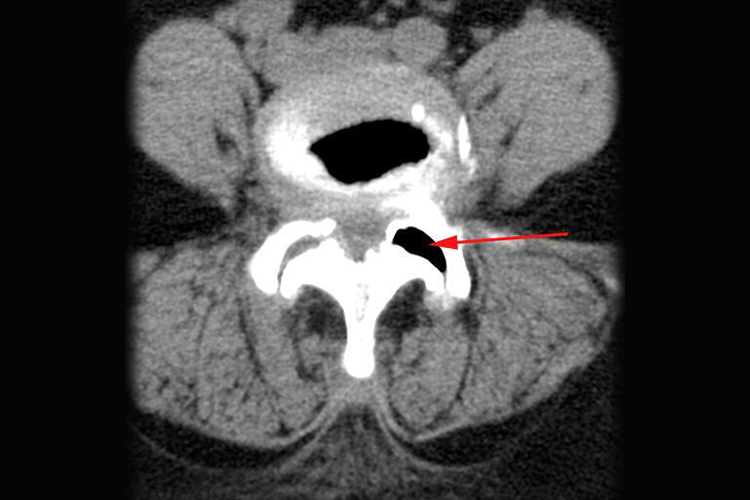

腰椎小关节紊乱影像学检查可见关节突增生,关节间隙增宽、对合不良,关节突关节退变,软骨下硬化,关节内碎骨、积液、积气等改变。同时患者还可伴有腰部疼痛,或牵扯到骶尾部、臀部疼痛,无下肢放射痛。腰椎关节突关节部位有明显压痛,但无向下的放射痛。